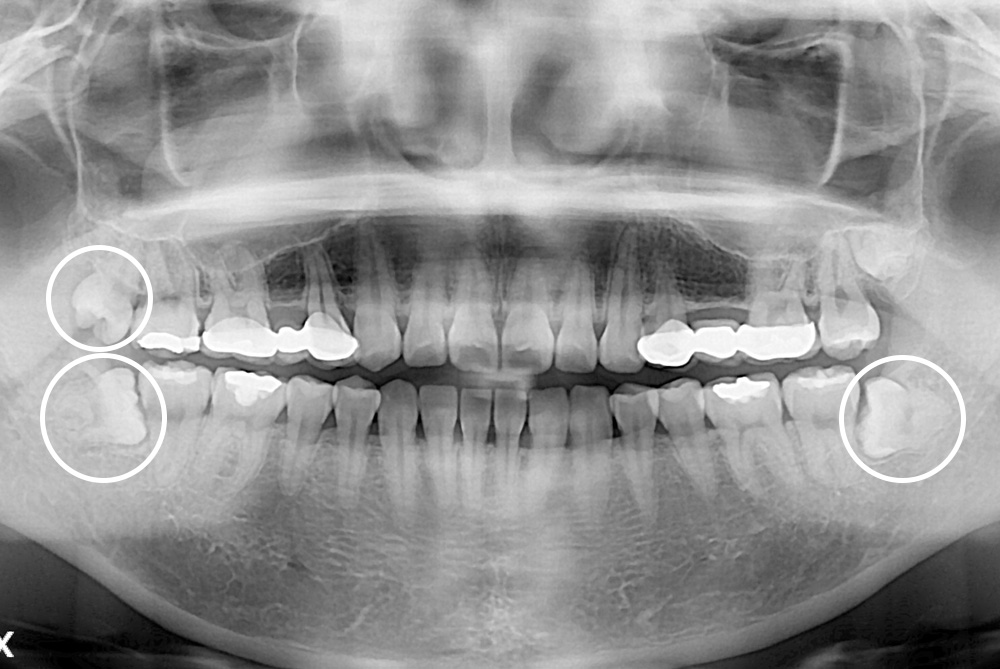

[사랑니] 매복 사랑니 발치

치료후 : 2022-09-09

세종치과는 구강악안면외과학 박사이신 원장님이 발치하는 치과입니다.